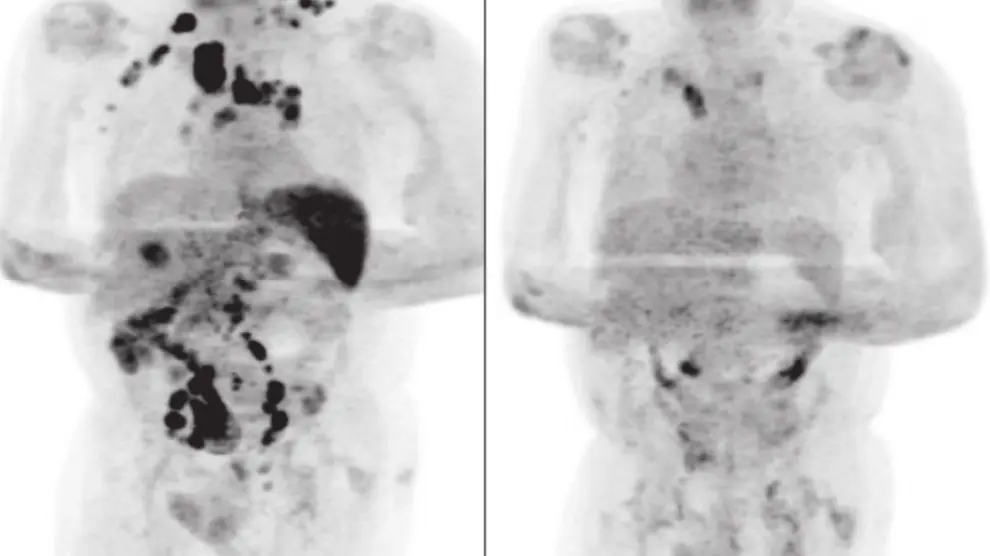

Lo que ha sorprendido a la comunidad científica es que tras recuperarse del virus, a los cuatro meses el hombre acudió al médico para una revisión del linfoma que padecía y las pruebas evidenciaron una disminución radical del tamaño de los ganglios afectados y una notable mejoría.

La principal hipótesis de los investigadores apunta a que la infección por SARS-CoV-2 desencadenó una respuesta inmunitaria antitumoral: las citocinas inflamatorias producidas en respuesta al virus podrían haber activando células que actuaron contra el tumor.